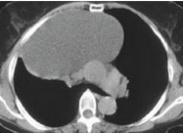

心包囊腫與心包憩室癥狀

• 心包囊腫與心包憩室

628健康網(wǎng)為您分享有關(guān)心包囊腫與心包憩室的癥狀,心包囊腫與心包憩室的治療方法,心包囊腫與心包憩室的預(yù)防知識(shí),心包囊腫...